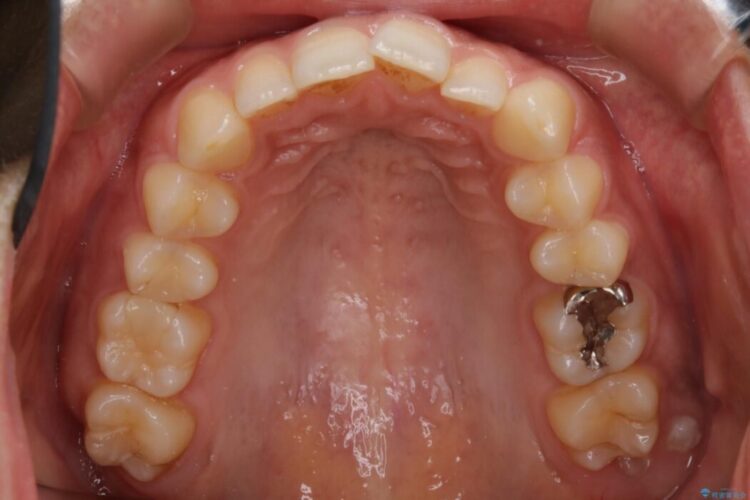

叢生の度合いにより抜歯は不要と判断しましたので、歯列幅の拡大を主軸に置き矯正治療を行いました。

本症例では下顎の歯列が舌側へ傾くことにより幅が狭まっていましたので、マウスピース治療により歯列弓を拡大しました。